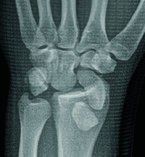

Palmar Divergent Dislocation of the Scaphoid and Lunate

Teaching Point: Palmar dislocation of the scaphoid and lunate is an extremely uncommon injury that warrants early diagnosis and treatment to avoid complications such as median nerve dysfunction, avascular necrosis, and premature osteoarthritis.